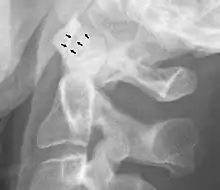

The atlanto-axial joint is a joint in the upper part of the neck between the atlas bone and the axis bone, which are the first and second cervical vertebrae. It is a pivot joint.

There is a pivot articulation between the odontoid process of the axis and the ring formed by the anterior arch and the transverse ligament of the atlas.

Abnormal widening

A widening of the atlanto-axial joint, as measured between the posterior surface of the anterior arch of atlas and the front of the odontoid process, indicates an injury to the transverse atlantal ligament.[5] Normally, this atlanto-dental distance is less than 2 mm, sometimes a maximum of 3 mm is accepted in men and 2.5 mm in women.[5]